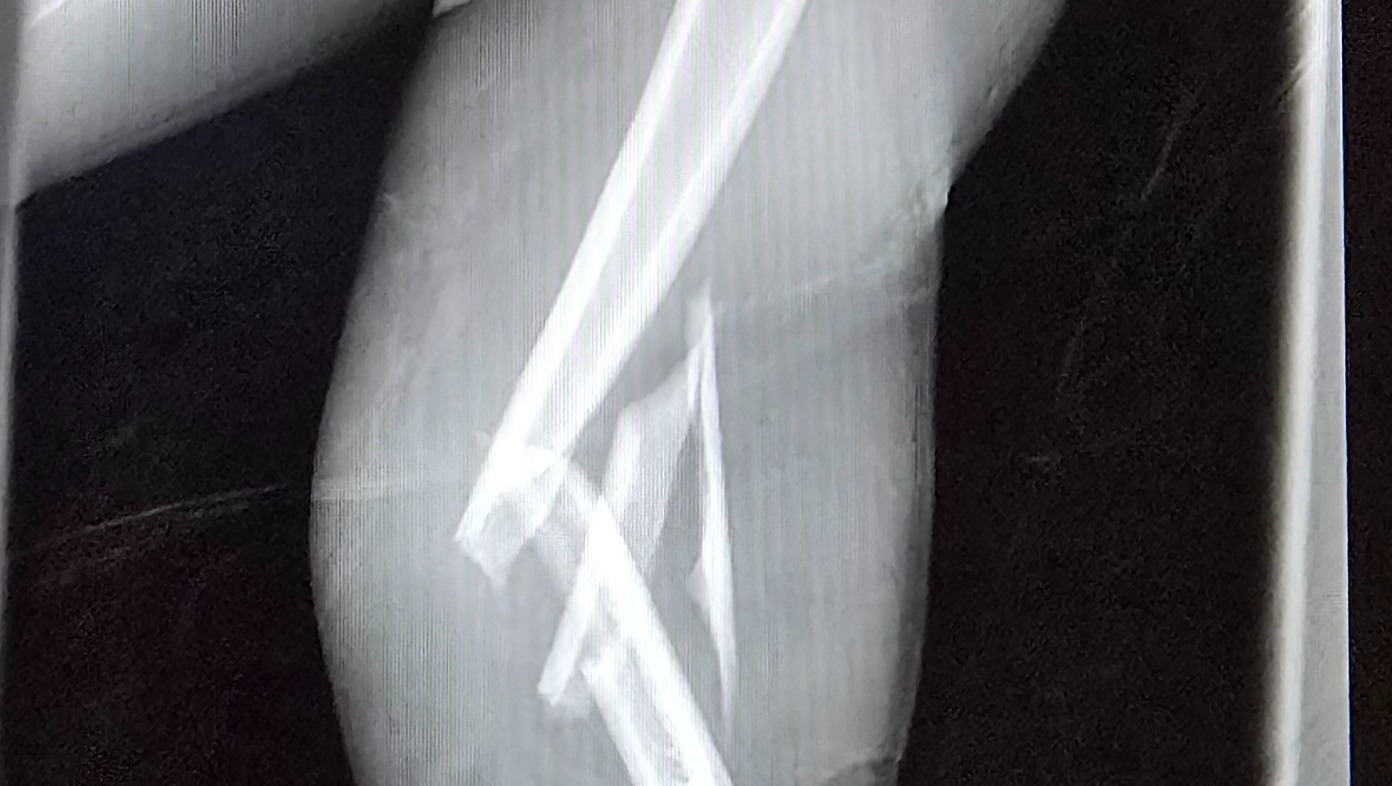

Even though he was wearing his seatbelt, the entire impact hit his left side. His left arm was shattered into multiple pieces, causing severe nerve damage. His left femur was broken into three pieces. He also struck his head against the window.

He was rushed to the hospital, where he spent a long night in unbearable pain before undergoing nearly eight hours of emergency surgery the next morning. Surgeons worked tirelessly to reconstruct his arm and leg. Today, Cole lives with metal rods and screws permanently placed in both his arm and leg.